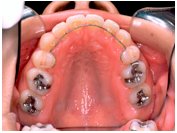

(注) この患者さんの治療の詳細は、院長の治療例の「叢生」(ここをクリック)で詳しく解説しておりますので、治療の方法や期間、治療費、リスク等はそちらを参照してください。